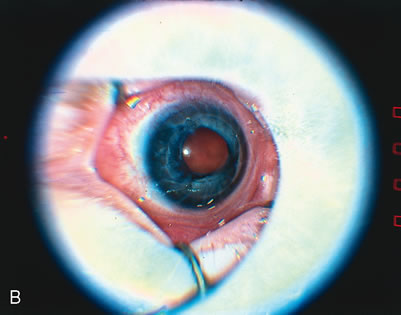

Fig. 2. A. Clinical appearance of stage 3 ROP. This stage has growth of vessels with fibrous tissue out of the plane of the retina (extraretinal fibrovascular proliferation). B. Clinical appearance of plus disease. In the posterior pole, the retinal veins are engorged and tortuous. C. Two representative eyes that have reached threshold for treatment. The right eye (RE) has at least eight accumulative clock hours of stage 3 ROP. The left eye (LE) has at least five contiguous clock hours of stage 3 ROP. The thin line of ROP represents stage 1 or stage 2 disease, the broader sketched line signifies stage 3 disease. (From Cryotherapy for Retinopathy of Prematurity Cooperative Group: Multicenter trial of cryotherapy for retinopathy of prematurity. Preliminary results. Arch Ophthalmol 106:471–479, 1988. Copyright, Archives of Ophthalmology.)

Threshold disease is defined as five contiguous or eight accumulated clock hours of stage 3 ROP with plus disease (Fig. 2). At threshold, the risk of 20/200 or worse final visual acuity is approximately 60% without treatment,10,11 and it is the level of disease at which treatment should be applied. When threshold disease is present, treatment should be performed within 72 hours of detection.13